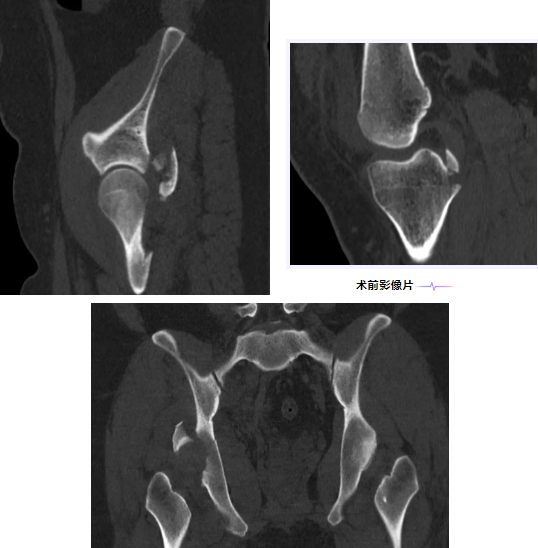

2026年1月18日,23岁的小张(化名)在骑电动车时不慎被小汽车撞倒,当即出现右髋、右膝剧烈疼痛,肢体活动完全受限,被紧急送往附近就诊。完善CT检查后,明确诊断为右髋臼骨折并股骨头脱位、右膝交叉韧带撕脱骨折,病情复杂且凶险。

髋臼骨折被誉为创伤骨科“皇冠上的明珠”,而股骨头脱位若处理不当,极易引发股骨头坏死等严重并发症,加之患者同时合并膝关节交叉韧带撕脱骨折,治疗难度大幅提升。更棘手的是,患者体重高达118公斤,给手术视野显露、骨折复位固定带来极大挑战,术中出血、组织损伤的风险也显著增加。在当地医院紧急就诊,给予手法复位脱位后,因手术难度过高、风险过大,建议患者转至上级医院进一步治疗。

焦急万分的患者及家属经熟人介绍,联系到市二医院骨一科业务主任饶放萍主任医师。饶主任详细了解患者病情、查看影像学资料后,结合患者体重特殊、伤情复杂的特点,果断建议患者转入市二医院接受手术治疗。患者及家属随即于当日入住市二医院骨一科,开启了救治之路。

为确保手术安全顺利,骨一科学科团队开展病例讨论,全面评估患者病情。手术专家团队充分考虑到患者体重大导致的手术视野暴露困难、出血风险高、复位难度大等问题,明确术中需遵循轻柔操作原则,精准控制创伤,减少出血。经过反复研讨,最终确定了最优手术方案——“右髋臼骨折切开复位内固定、植骨+右膝交叉韧带重建+胫骨髁间骨折切开复位内固定术”,一次性解决多处损伤,避免患者承受多次手术的痛苦。